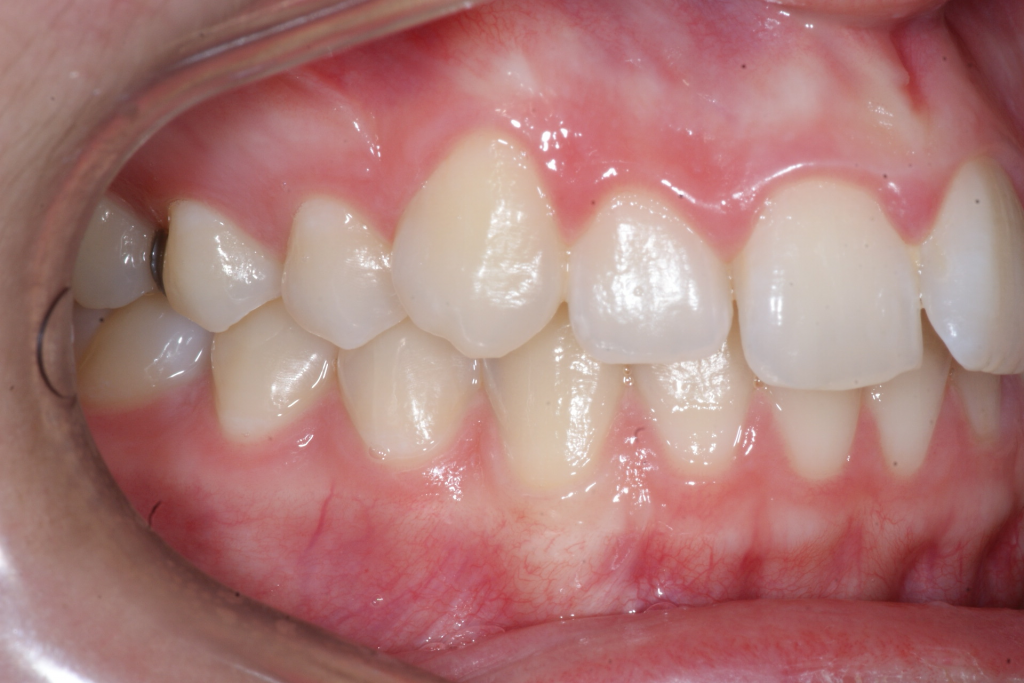

Correction d’une malocclusion de type Classe II division 1, surplomb horizontal inadéquat et chevauchement modéré aux 2 arcades. Des appareils fixes (broches et vis d’expansion) et des élastiques furent nécessaires pour améliorer ce sourire. Traitement chez une adolescente, réalisé en 18 mois.